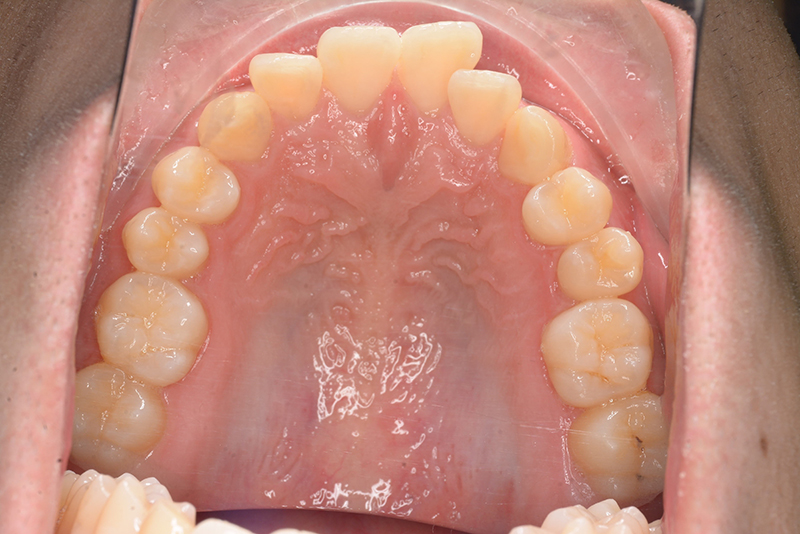

動的治療終了時

批評・予后 左側臼歯uprightによって鋏状咬合、過蓋咬合の改善が得られた。下顎前歯先欠によるAnterior ratio不調和と上顎前歯部叢生の改善を目的とし、上顎前歯にIPRを行ったが、治療後において左上2付近のover jetが大きく、上顎犬 歯間幅径の拡大(1.5mm)も生じているため、後戻りの懸念が残る。口元や歯列の安定性を考慮し、小臼歯抜歯も検討したがハイアングルであり下顎3-incisalのため、治療が困難となる事を危惧して非抜歯にて治療を行った。